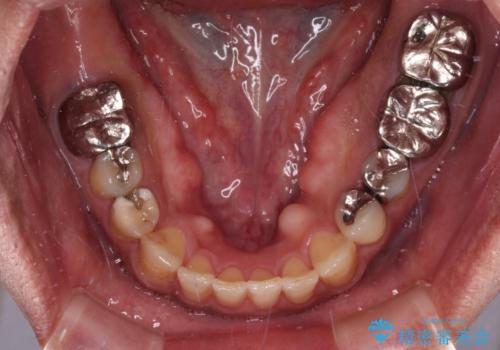

- 咬み合わせの悪さを気にして来院された患者様です。

来院当初は、奥歯の銀歯が問題で咬み合わせが悪いと思っていらっしゃいましたが、前歯の反対咬合を改善することが最優先とご説明し、矯正治療を行うこととしました。

奥歯には抜歯が必要な歯があったため、事前に抜歯を行い、その後ワイヤー装置にて治療を開始しました。